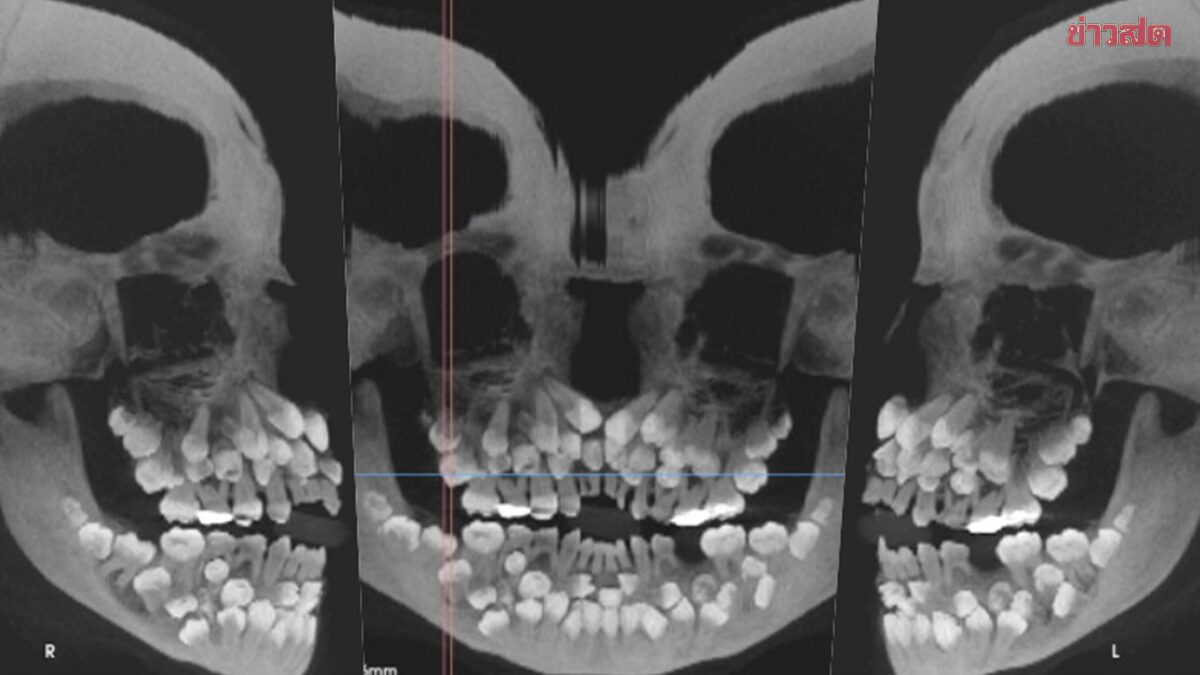

เด็กหญิงคนหนึ่งอายุ 11 ปี 8 เดือนในเมืองมีนัสเชไรส์ ประเทศบราซิล ได้เข้ารับการตรวจสุขภาพช่องปากที่คลินิกทันตกรรม เนื่องจากเธอวางแผนที่จะถอนฟันน้ำนมแถวบนที่ยังไม่หลุด อย่างไรก็ตาม ภาพเอกซเรย์เผยให้เห็นการค้นพบที่น่าตกใจ นั่นคือ จริง ๆ แล้วเธอมีฟันน้ำนม 18 ซี่ ฟันแท้ 32 ซี่ และฟันเกินอีก 31 ซี่ในช่องปาก รวมเป็นฟันทั้งหมด 81 ซี่

จากการตรวจในช่องปาก แพทย์บันทึกไว้ว่ามีเพียงฟันแท้ 5 ซี่ที่งอกออกมาแล้ว ในขณะที่ฟันน้ำนมยังคงมีอยู่จำนวนมาก เพื่อประเมินสภาพฟันและช่องปากของผู้ป่วยเด็กให้ครบถ้วนมากขึ้น แพทย์จึงสั่งให้ถ่ายภาพเอกซเรย์แบบภาพรวมและภาพกะโหลกศีรษะด้านข้าง

อีกทั้งภาพเหล่านี้ยังแสดงให้เห็นว่าฟันหลายซี่มีรูปร่างผิดปกติ ฝังลึกอยู่ในเหงือก ทำให้การแยกแยะระหว่างฟันปกติและฟันส่วนเกินเป็นเรื่องที่ยากลำบากอย่างมาก ซึ่งผู้ใหญ่ทั่วไปควรมีฟัน 32 ซี่ และฟันที่เกินมานี้เรียกว่า “ฟันเกิน” โดยทั่วไปจะมีฟันเกินเพียง 1 – 2 ซี่เท่านั้น